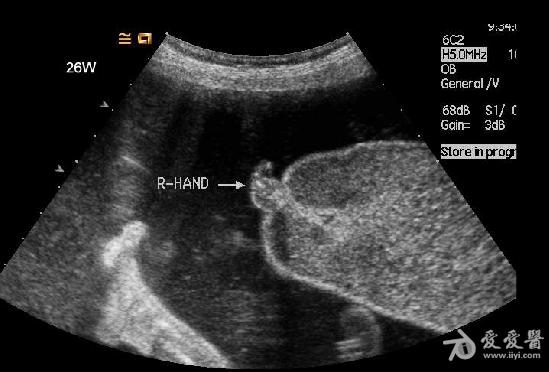

是双胎,其中畸形的那个明显没有上半身及头部,只有下半身和一点点短小的左上肢。

1、双胎中一胎形态、结构发育正常,另一胎出现严重畸形,以上部身体严重畸形为主,可有下部身体如双下肢等结构。

3、上部身体严重畸形,可表现为无头、无双上肢、胸腔发育极差。